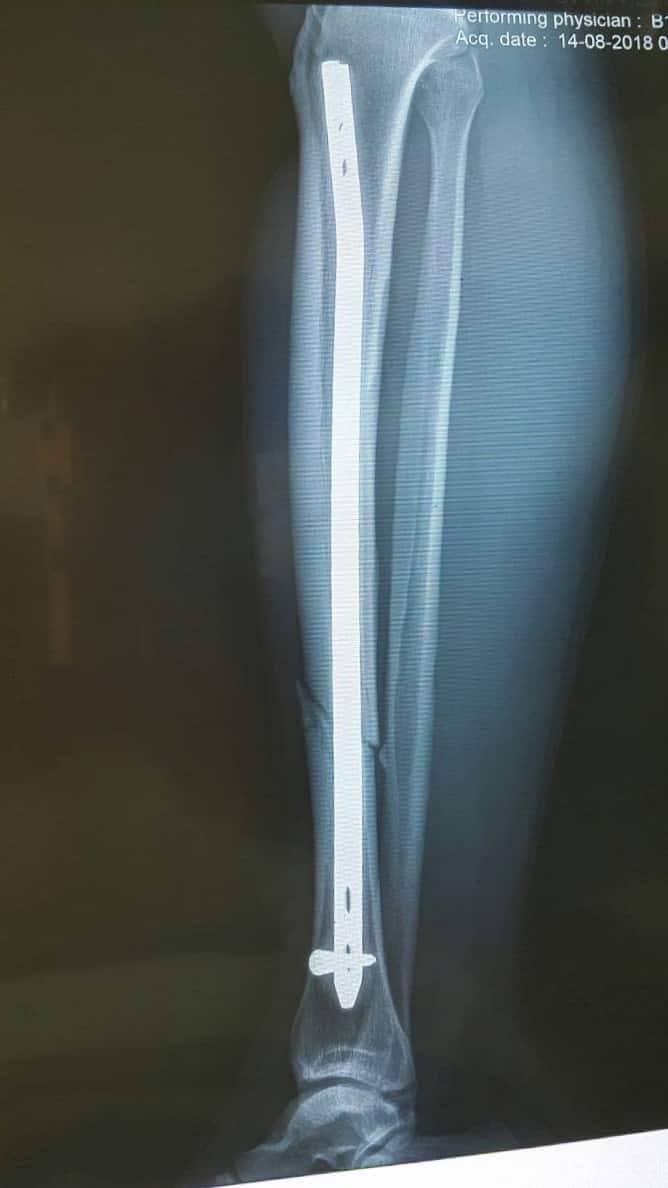

Sau khi chẩn đoán, xác định đại uý Tuyền bị gãy kín 1/3 giữa xương chày phải. Tình trạng toàn thân ổn định, cần hạn chế vận động cẳng chân phải.

Ngay lập tức các bác sĩ đã tiến hành phẫu thuật đóng đinh nội tủy xương chày phải có chốt dưới màn tăng sáng, không mở vào ổ gãy. Sau phẫu thuật hiện tại tình trạng sức khoẻ của đại uý Tuyền đã dần ổn định.

Vị trí xương gãy.